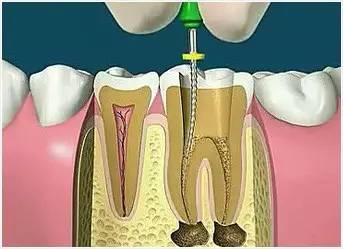

5、根管沖洗、消毒

根管沖洗的目的是清除微生物、沖掉殘渣,潤滑根管器械和溶解有機(jī)殘渣。然后,再進(jìn)行根管消毒,使根管內(nèi)達(dá)到無菌狀態(tài)。

6、根管充填

封閉整個根管系統(tǒng)、堵塞主根管和側(cè)副根管出口、防止微生物和液體的滲漏。無論是側(cè)方加壓法還是垂直加壓法,應(yīng)做到根管充填致密,根管充填后X線片上無根管腔隙,也不能超出根尖孔。